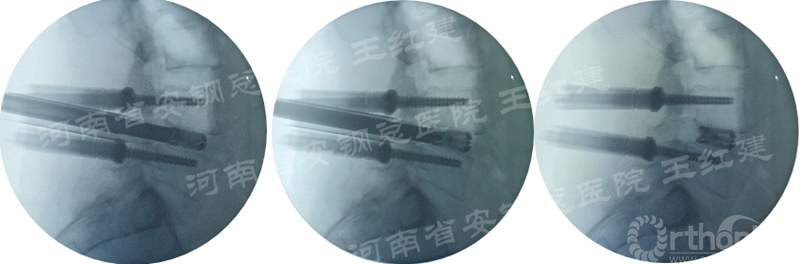

四、经皮螺钉技术固定

在固定的步骤可以先期进行经皮螺钉置入,再进行融合器的置入,进而实现充分固定。

椎弓根植入加压固定

单边椎弓根植入加压固定

双侧椎弓根植入加压固定

手术步骤:先期经皮螺钉置入、再进行融合器的置入